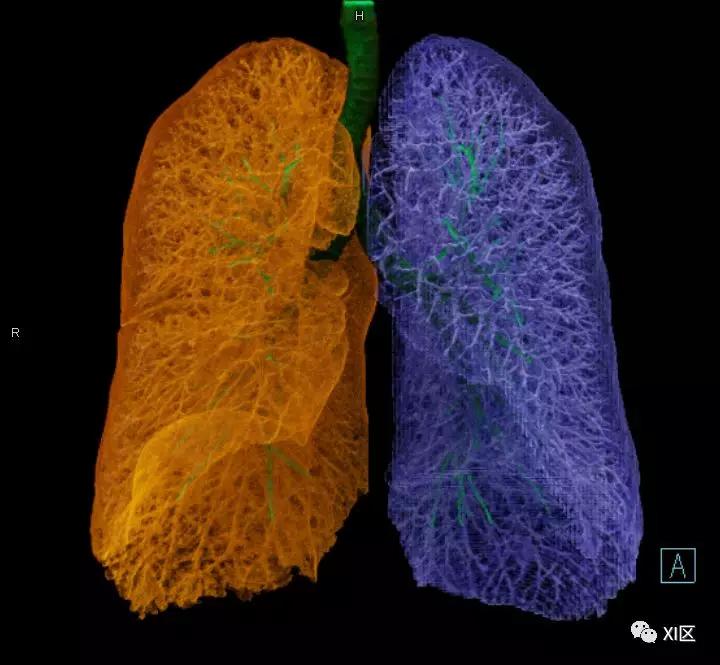

气管支气管树与两肺融合显示

气管树的解剖

人的支气管(第1级)至肺泡约有24级分支。支气管经肺门入肺,分为叶支气管(第2级),右肺3支,左肺2支。叶支气管分为段支气管(第3~4级),左肺8支、右肺10支。段支气管就是肺的分段的依据。段支气管反复分支为小支气管(第5~10级),继而再分支为细支气管(第11~13级),细支气管又分支为终末细支气管(第14~16级)。从叶支气管至终末细支气管为肺内的导气部。终末细支气管以下的分支为肺的呼吸部,包括呼吸细支气管(第17~19级)、肺泡管(第20~22级)、肺泡囊(第23级)和肺泡(第24级)。

气管支气管形如树状,因此也称气管支气管树。

气管树

气管树与左右肺的关系